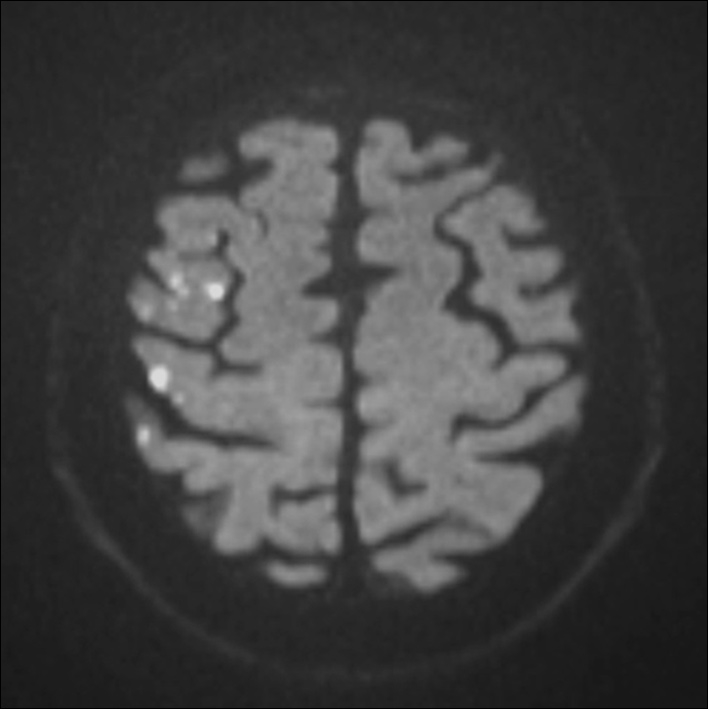

Figure 3

Diffusion weighted MRI of a patient following stenting of the right carotid artery in the MRI substudy of the International Carotid Stenting Study. Multiple hyperintense signals representing acute ischaemic lesions in the territory of the right middle cerebral artery are present. The patient did not experience any symptoms. © Department of Radiology, University Hospital Basel. Reprinted with kind permission.

Silent cerebral ischaemia

In carotid revascularisation, cerebral ischaemia may occur without overt symptoms of stroke or TIA. Transcranial Doppler sonography and diffusion-weighted brain imaging (DWI), a magnetic resonance sequence which is highly specific and sensitive to acute cerebral ischaemia, have been used to detect subclinical embolic events in CAS and CEA. A systematic review of non-randomised studies using DWI before and after treatment showed that an average of 37% of patients had new ischaemic lesions after CAS, compared with 10% of patients after CEA [21]. Within ICSS, a multi-centre prospective substudy investigated 124 patients randomised to CAS and 107 patients randomised to CEA with DWI before and after treatment [22]. 50% of CAS patients and 17% of CEA patients had new ischaemic lesions on DWI after treatment (OR 5.21, 95% CI 2.78–9.79, p <0.0001; fig. 3). Since assessment of MRI could be done without knowledge of the allocated treatment, these results argued against the presence of bias explaining the observed differences in rates of clinically manifest strokes. Furthermore, the use of DWI allowed detecting differences between treatments which were consistent with the clinical outcomes of the main trial in only a fraction of the study population. Therefore, DWI may potentially serve as a surrogate outcome measure in future pilot studies evaluating new treatment strategies or investigating disease mechanisms [21].